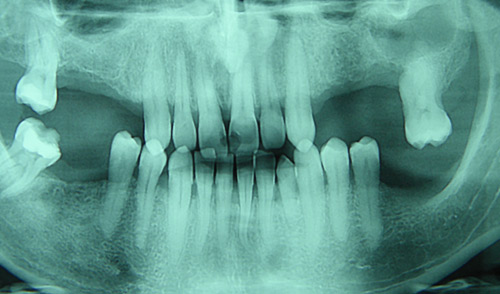

• ciste vilica; operativno liječenje (cistektomije)

• ekstrakcije zuba

• komplikovane ekstrakcije

• ekstrakcije impaktiranih zuba